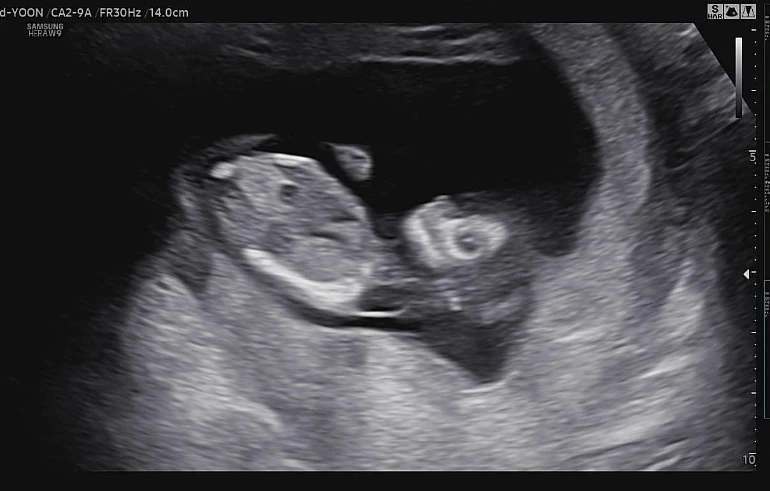

뚜렷한 얼굴뼈가 보여 원숭이 같다.

지난번 보다 좀 더 커진 아기. 얼굴 이목구비가 전보다 뚜렷해졌고, 다리길이도 더 길어졌다. 척추뼈도 선명하게 보였다. 이제 소화기능도 생겨서 양수를 마신 흔적까지 확인할 수 있었다. 머리 쪽을 확인하며 뇌의 모양도 나비모양으로 잘 자라고 있다고 했다. 선생님은 "코가 엄청 높네요ㅎㅎ"라고 하셨는데, 내가 봐도 코가 높은 것 같기도 하고, 코가 또치처럼 생긴 것 같기도 했다. 남편과 내 코가 낮은 편은 아니니까 우리 띠용이 코도 낮진 않겠지? 하는 기대감이 생긴 순간이다.